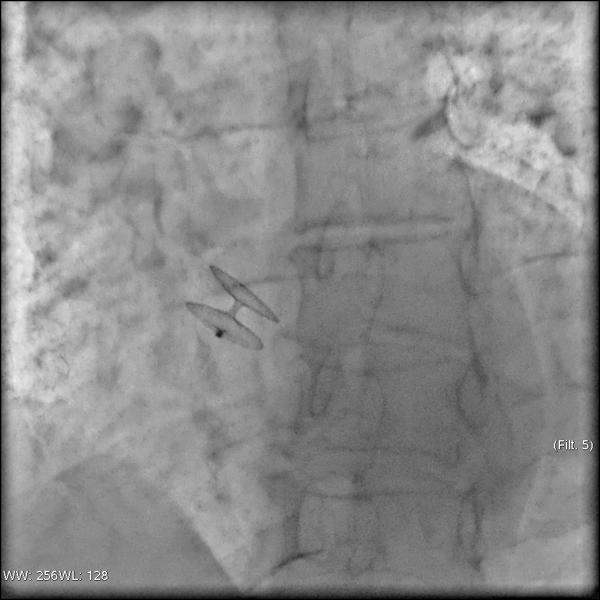

Как проводится хирургическое лечение открытого овального окна? Транскатетерное закрытие аномалии межпредсердной перегородки осуществляется с применением специализированных окклюдерных систем. Процедура проводится под контролем рентгеноскопии и эхокардиографии. Методика включает введение катетера с окклюзионной конструкцией через бедренную вену до достижения правого предсердия. После позиционирования устройства оно раскрывается и надежно фиксируется по обе стороны дефекта в межпредсердной перегородке, обеспечивая эффективное закрытие овального отверстия. В Волынской больнице специалисты первого кардиологического отделения и отделения рентгенохирургических методов диагностики и лечения проводят подготовку и выполняют данный вид хирургического эндоваскулярного вмешательства.